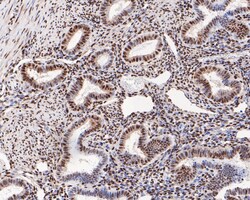

Invitrogen™ Phospho-ATF2 (Thr71) Recombinant Rabbit Monoclonal Antibody (SC05-90)

The transcription factor ATF-2 (also called CRE-BP1) binds to both AP-1 and CRE DNA response elements and is a member of the ATF/CREB family of leucine zipper proteins. ATF-2 interacts with a variety of viral oncoproteins and cellular tumor suppressors and is a target of the SAPK/JNK and p38 MAP kinase signaling pathways. Various forms of cellular stress, including genotoxic agents, inflammatory cytokines and UV irradiation, stimulate the transcriptional activity of ATF-2. Cellular stress activates ATF-2 by phosphorylation of Thr69 and Thr71. Both SAPK and p38 MAPK have been shown to phosphorylate ATF-2 at these sites in vitro and in cells transfected with ATF-2.

| Immunohistochemistry (Paraffin), Western Blot, Immunocytochemistry | |